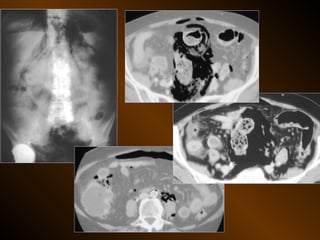

KHÍ TỰ DO

TRONG KHOANG PHÚC MẠC

NGUYÊN NHÂN

thủng tạng rỗng

nguồn gốc xuyên phúc mạc

nguồn gốc trong phúc mạc

10 – 15% thủng tạng rỗng → không thấy hơi tự do ổ bụng

TỤ KHÍ NGOÀI PHÚC MẠC

• Nguyên nhân :

– Thủng tạng rỗng

– Áp xe tạo khí

• X quang quy ước

• Siêu âm

• XQCLĐT